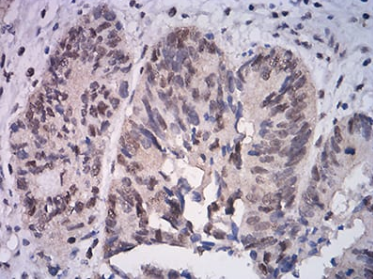

IHC    1/200 - 1/1000